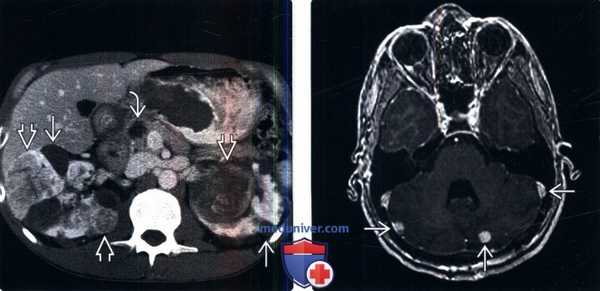

(Слева) КТ с контрастированием, аксиальная проекция: у пациента с болезнью Гиппеля-Линдау выявлены множественные двусторонние кисты почки и ПКР. Выявлено кистозное новообразование в головке поджелудочной железы. Поджелудочные проявления болезни Гиппеля-Линдау включают кисты, кистозные новообразования (микрокистозная аденома) и нейроэндокринные опухоли.

(Справа) МРТ, постконтрастное Т1-ВИ, аксиальная проекция: выявлены множественные контрастируемые патологические изменения мозжечка, что позволяет предположить гемангиобластомы.